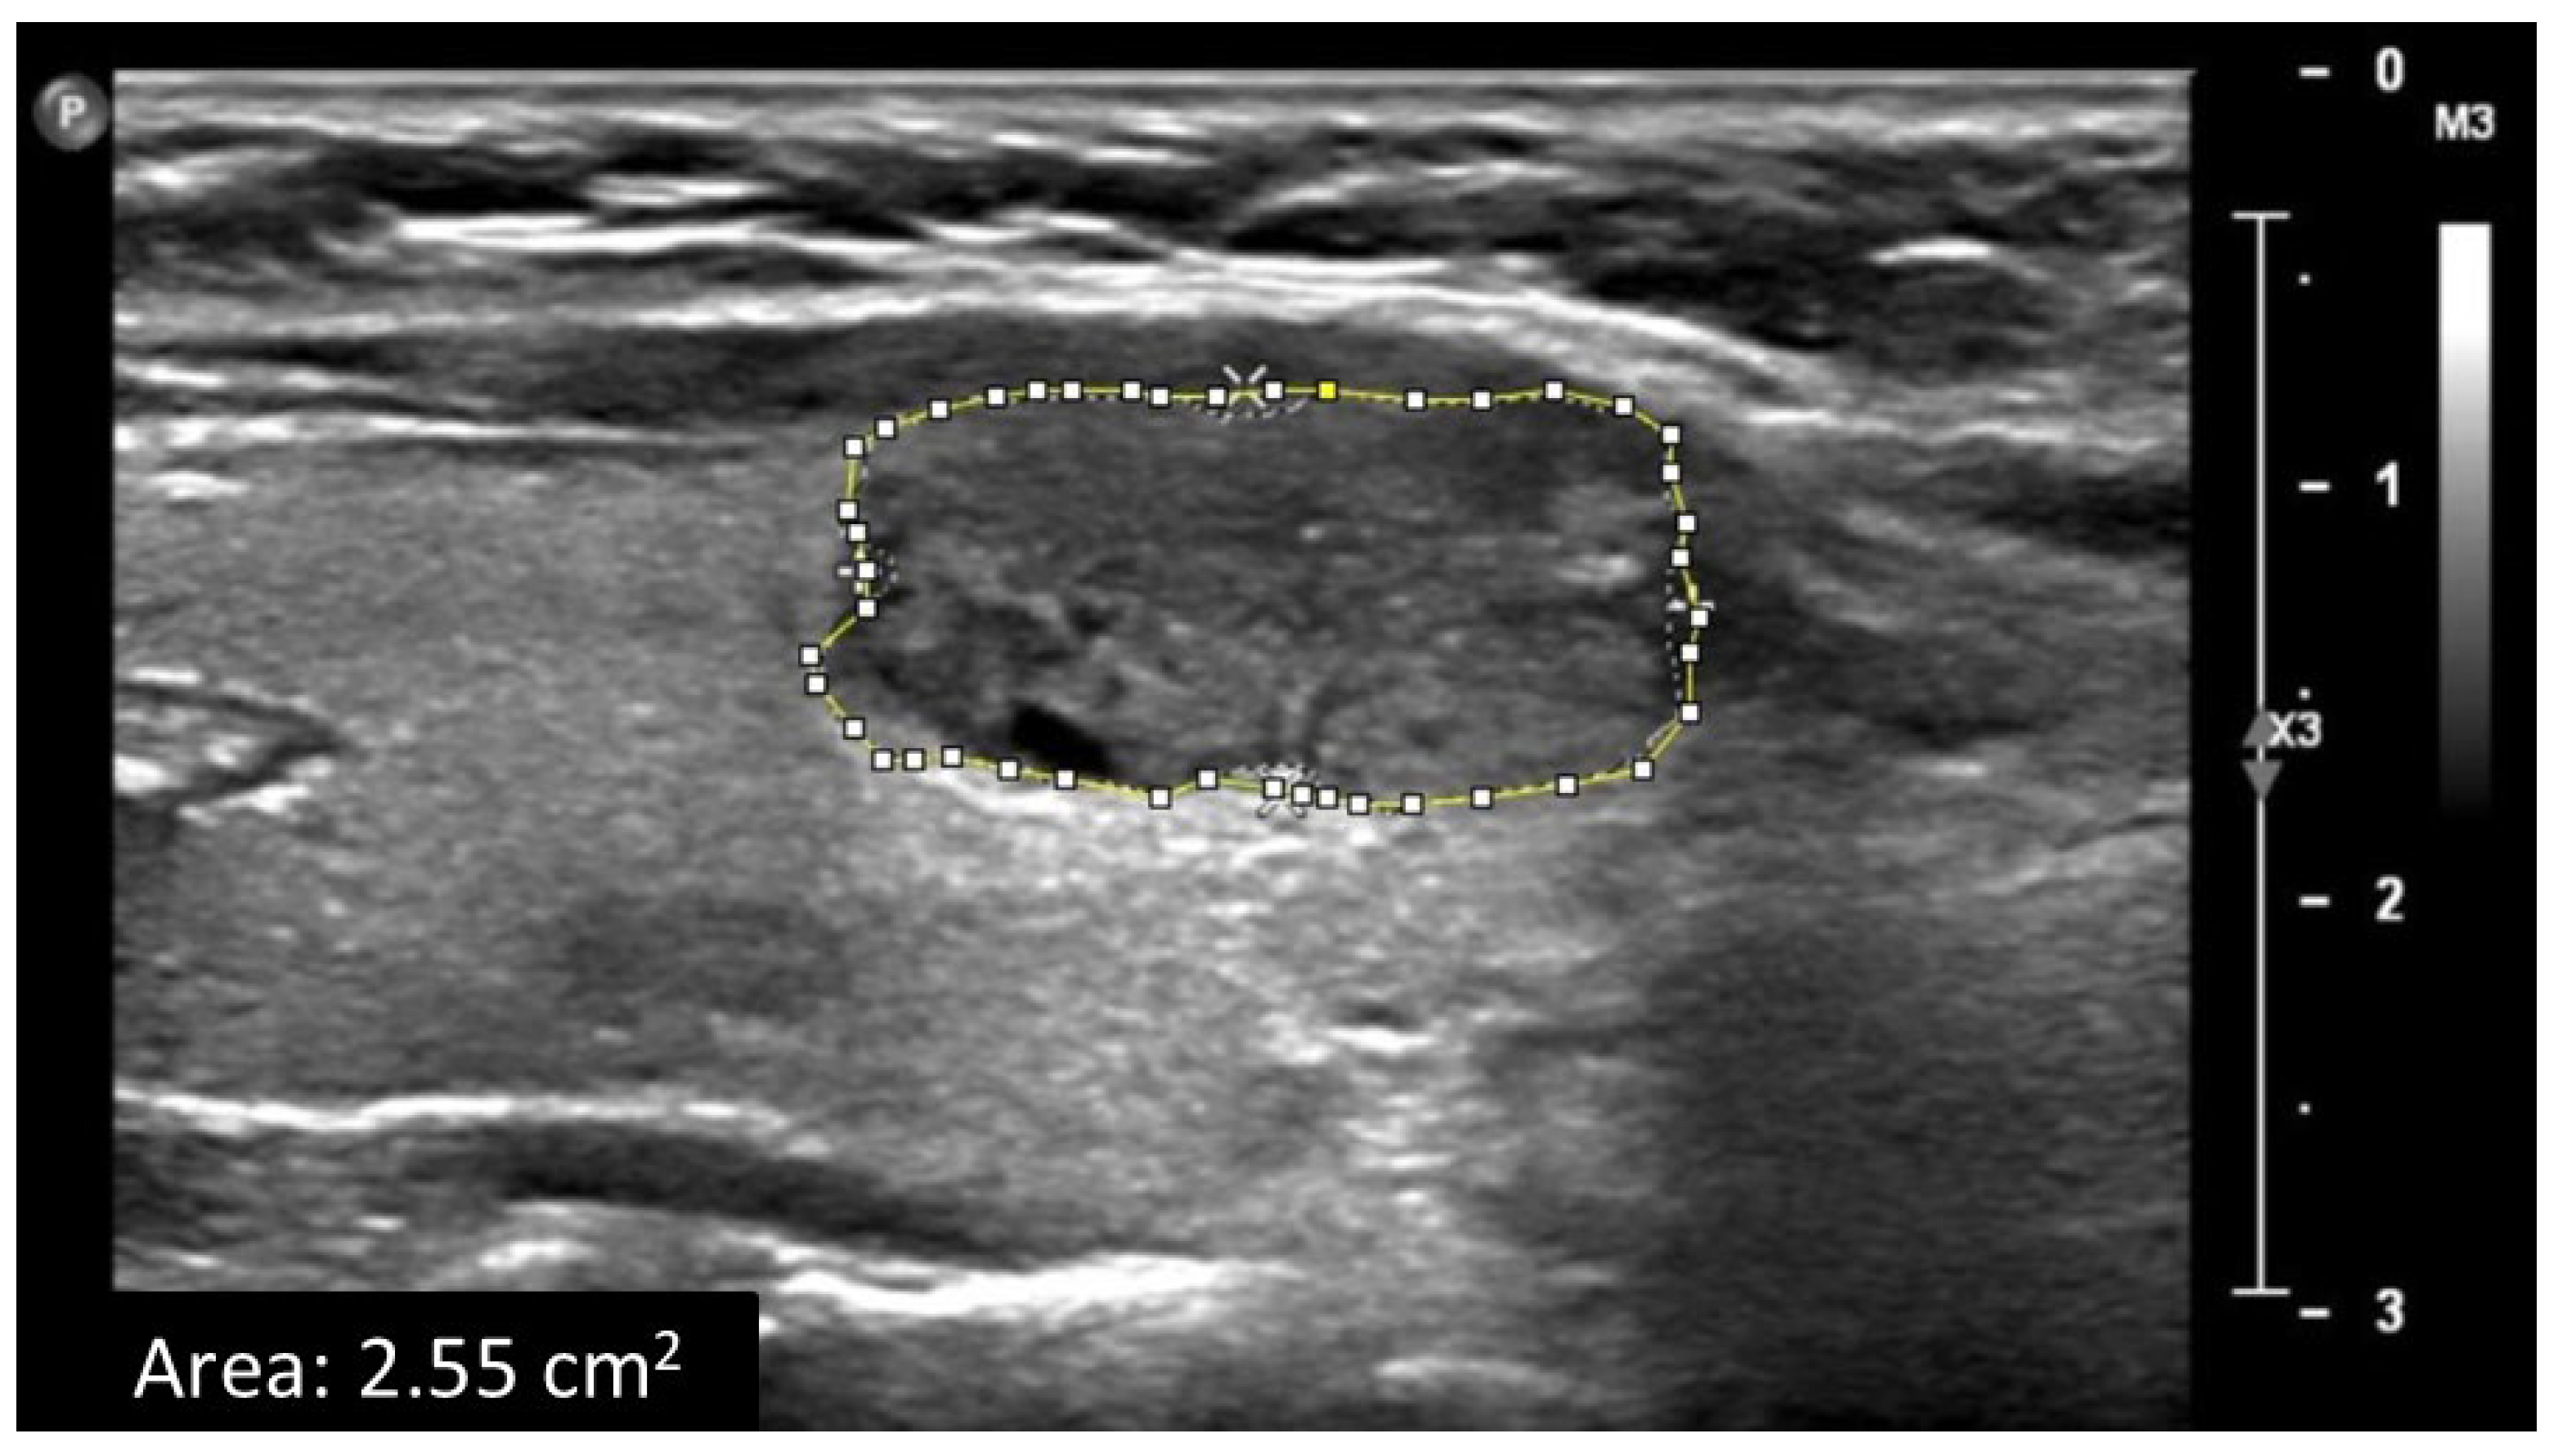

2.2. Data Acquisition and Ultrasound Image Analysis